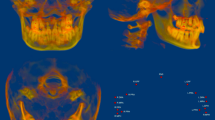

CBCT images (NewTom VGi [QRsrl, Verona, Italy]) were taken before the treatment (T0) and on the day of orthodontic appliance removal (T1). The resulting images were imported into Mimics Medical 21.0, the 3D measurement software (Materialise, Belgium). The orbital–ear, mid–sagittal, and coronal planes perpendicular to both planes were used as 3D reference planes. Pretreatment (T0) and post-treatment (T1) craniofacial bone and teeth 3D images were extracted, and landmark localization and index measurement were performed (Fig. 1). Detailed operations are as follows:

To accurately analyze changes in the zygomatic pillar after orthodontic tooth movement, external reference lines, constructed from stable skeletal structures, were used to define the range. (1) Coronal range (horizontal): between the IF plane and the buccal lateral margin (Fig. 2). (2) Sagittal range: between the OR plane and the TSZ plane (Fig. 3). (3) Vertical range: between the FMT plane and the M1 plane. The FMT, FH, and DMF planes divided the vertical range of the zygomatic pillar into upper, middle, and lower segments, respectively (Fig. 4). Changes in the morphology of the zygomatic pillar were assessed. The cross-sectional area of the zygomatic pillar was measured as follows: The lower segment was divided into thirds and the middle segment into halves, resulting in seven height planes, namely h1–h7 (Fig. 5).

Changes in the cross-sectional area in the seven stable height planes were measured within the fixed pillar range before and after the treatment to reflect changes in the overall morphology of the zygomatic pillar (Fig. 6). The surface morphology landmark of the zygomatic pillar was analyzed as follows: The following four landmarks were located in the zygomatic pillar area: △ZFF, △ZP, △ZM, and △EKM (Fig. 7). Using Mimics, the pretreatment and post-treatment 3D models of the same patient were overlaid to analyze changes in the coordinates of the landmarks using the coordinate system of the software, thereby reflecting changes in the surface morphology of the zygomatic pillar (Fig. 8).